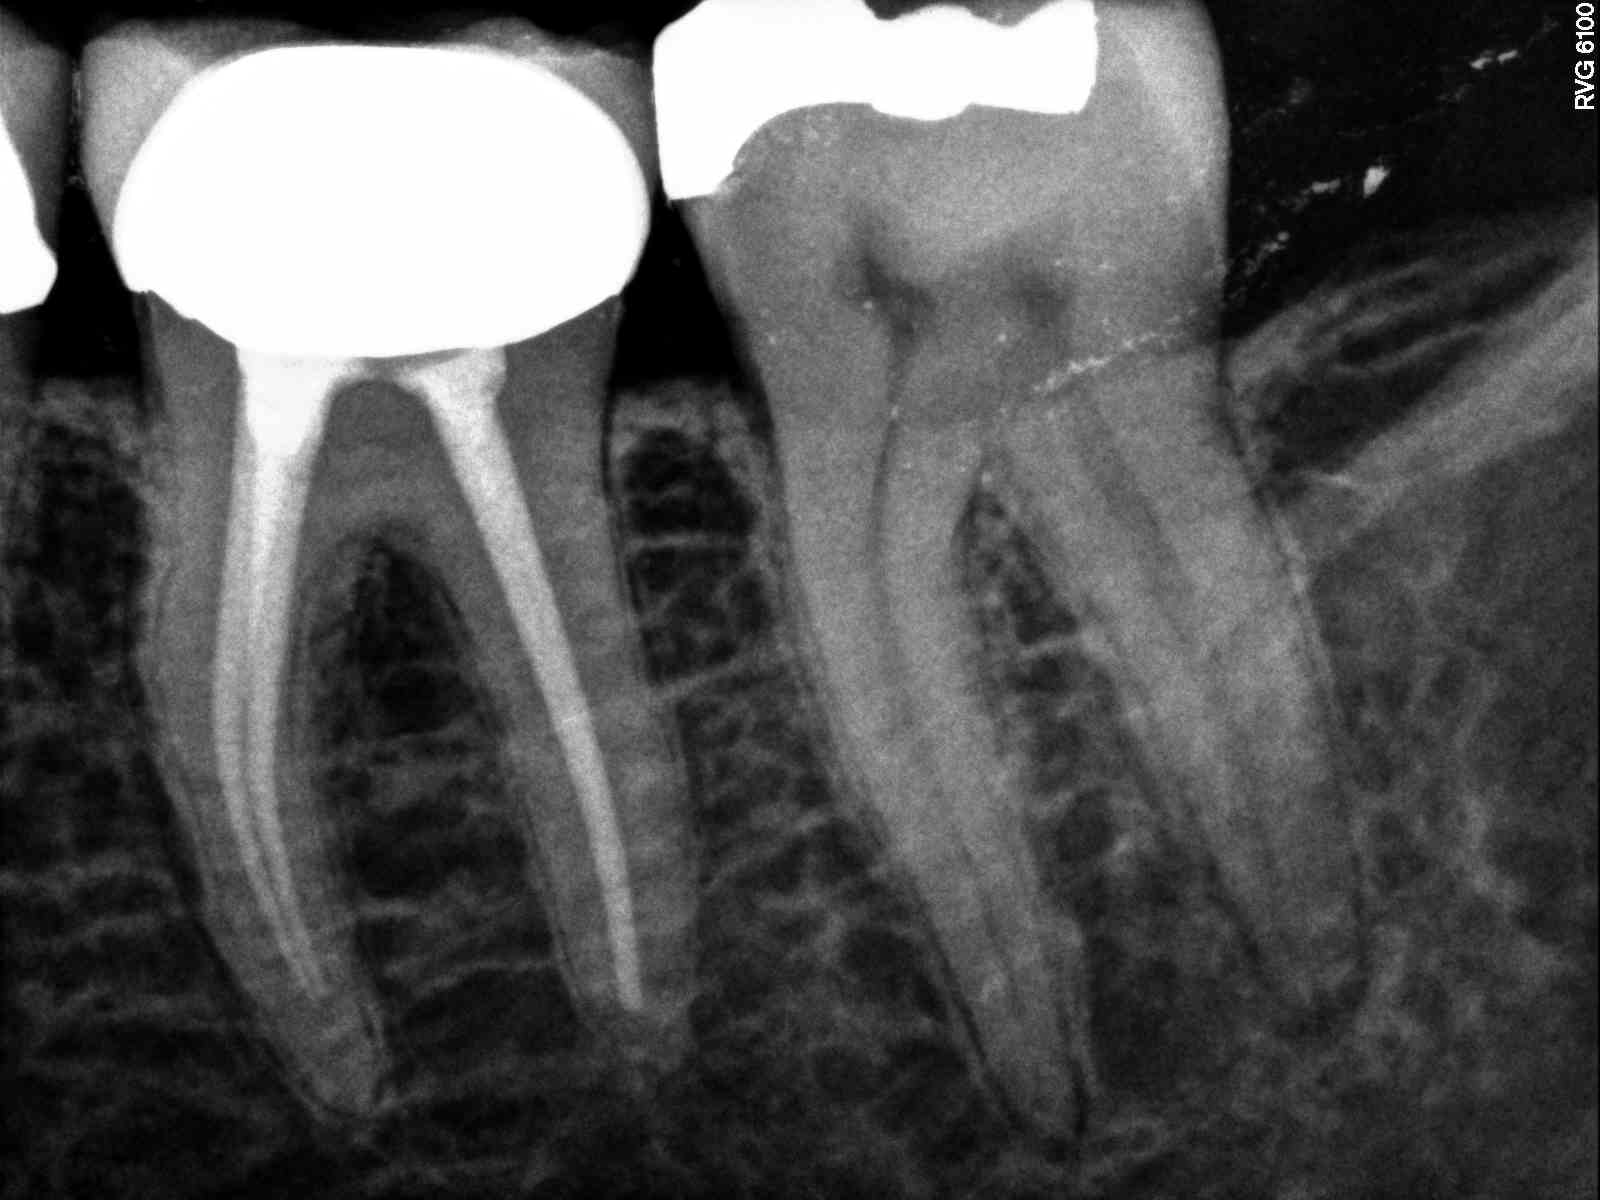

Small piece white path file separated past apex in distal. Normal anatomy

| Can see file in distal canal heading mesially at apex |